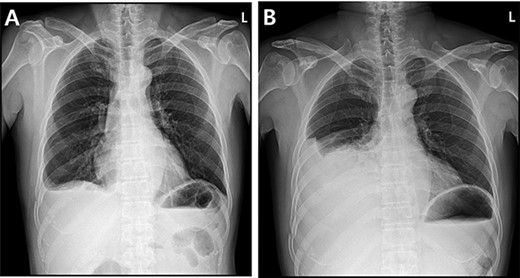

A 59-year-old man was admitted with multiple rib fractures and liver contusion due to a fall injury. He was standing on a chair for working at a farm, and it was knocked over causing him to fall and hit his flank against the corner of the chair. There was continuous pain while resting at the right flank and severe pain with pressure was noted, but no external wounds or bruises were observed. There were right 7th–11th rib fractures, scanty pneumothorax, minimal hemothorax and a 2-cm-sized liver contusion in abdomen and chest computed tomography (CT) scan (Fig. 1A, B). He was hospitalized for pain control and close observation in the general ward, and conservative management was initiated. Also, no significant changes were noted in the following daily follow-up chest radiographs. The patient suddenly complained of right-sided chest and back pain aggravation, cold sweating and fatigue 80 h after the traumatic injury. His mental status was alert, but v/s including systolic blood pressure (SBP) of 100–120 mmHg, heart rate (HR) of 40-60 beats/min and oxygen saturation of 100% during the admission changed to an SBP of 86/60 mmHg, HR of 88 beats/min and oxygen saturation of 97% when the symptoms occurred. Chest radiography was performed after the patient experienced aggravated symptoms, such as right-sided flank pain, cold sweating and fatigue. Compared to the previous scans, signs of increased opacification and peribronchial and parenchymal infiltrations were observed, which were indicative of hemothorax (Fig. 2A, B). We performed enhanced dynamic chest CT to identify any presence of active bleeding. On the chest CT scan, a large amount of hemothorax was identified in the right lung field along with multiple fractures of the right ribs. However, there were no signs of contrast leakage indicative of active bleeding (Fig. 3). Hemoglobin levels decreased from 13.1 g/dl on the day before the symptoms appeared to 11.5 g/dl at the onset of symptoms and to 9.4 g/dl after 2 h. Four packs of RBC transfusion and fluid were administered to the patient, and he was moved to the intensive care unit for close monitoring. And tube thoracostomy was performed, and 1600 ml of fresh blood was drained (Fig. 4A). The following day, 500 ml of blood was drained through the chest tube, but his v/s were stable (Fig. 4B). The amount of bleeding through the chest tube was decreased, but the drained fluid was fresh blood. And we thought that the remaining hematoma was not effectively drained, so the patient’s respiratory discomfort could persist and cause uneffective ventilation. And then we consulted with the Department of Thoracic Surgery, and video-assisted thoracoscopic surgery (VATS) exploratory thoracotomy was performed to identify the bleeding source caused by displaced rib and evacuate the large amount of hematoma. There was a large volume of hematoma within the pleural space and between the right lower lobe, diaphragm and fissure, but no active bleeding point was located. The fractured right 10th rib pierced through the pleural space and was displaced to the thoracic cavity, which was easily reduced. There was no injury surrounding the diaphragm, and although the general lung and chest wall contusions were severe, there were no signs of lung parenchymal lacerations (Fig. 5A–C). Chest tube drainage was serous, and there was no further bleeding. There were no signs of bleeding or any other abnormal findings on chest CT performed at the outpatient clinic, and the patient had no complaints of any symptoms (Fig. 6A, B).

Radiographic findings. (A) Day of symptoms, chest X-ray in the morning. (B) Chest X-ray after symptoms develop.